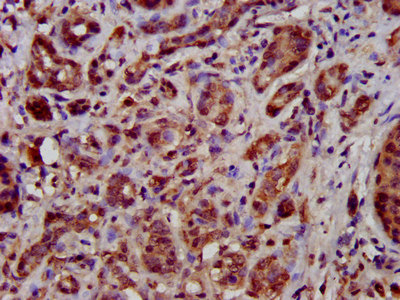

IHC image of CSB-PA023420LA01HU diluted at 1:500 and staining in paraffin-embedded human liver cancer performed on a Leica BondTM system. After dewaxing and hydration, antigen retrieval was mediated by high pressure in a citrate buffer (pH 6.0). Section was blocked with 10% normal goat serum 30min at RT. Then primary antibody (1% BSA) was incubated at 4°C overnight. The primary is detected by a biotinylated secondary antibody and visualized using an HRP conjugated SP system.